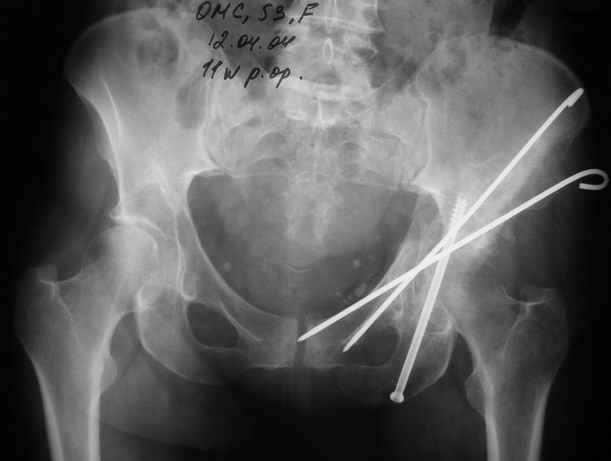

Не дождавшись советов, в понедельник прооперировал больного, заняло времени..., но все сделал в один этап: сначала фиксировал ипсилатеральный перелом бедра и шейки реконструктивным гвоздем Smith&Nephews, потом из расширенного илеофеморального доступа фиксировал перелом крыла подвздошной кости тягловым винтом, нейтрализующей пластиной заднюю колонну, и тягловыми винтами 3,5 мм переднюю колонну.

12.04.04